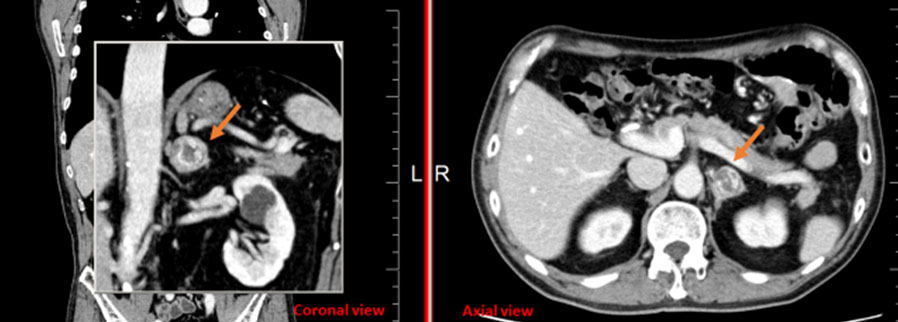

Systemic amyloidosis causing profound retroperitoneal and perinephric calcified deposits

Keywords: Amyloidosis, Lymphoplasmacytic lymphoma, Retroperitoneal calcifications, Systemic amyloidosis